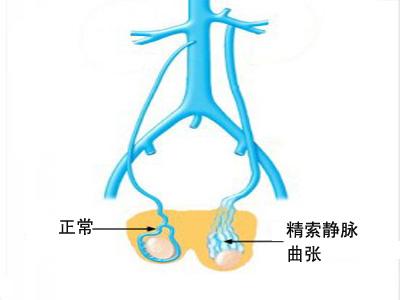

精索静脉曲张的定义是阴囊静脉异常扩张,约15%的正常男性和高达40%的不孕症男性存在精索静脉曲张。通常容易触及的较大的精索静脉曲张明显与不孕有关。精索静脉曲张和不...